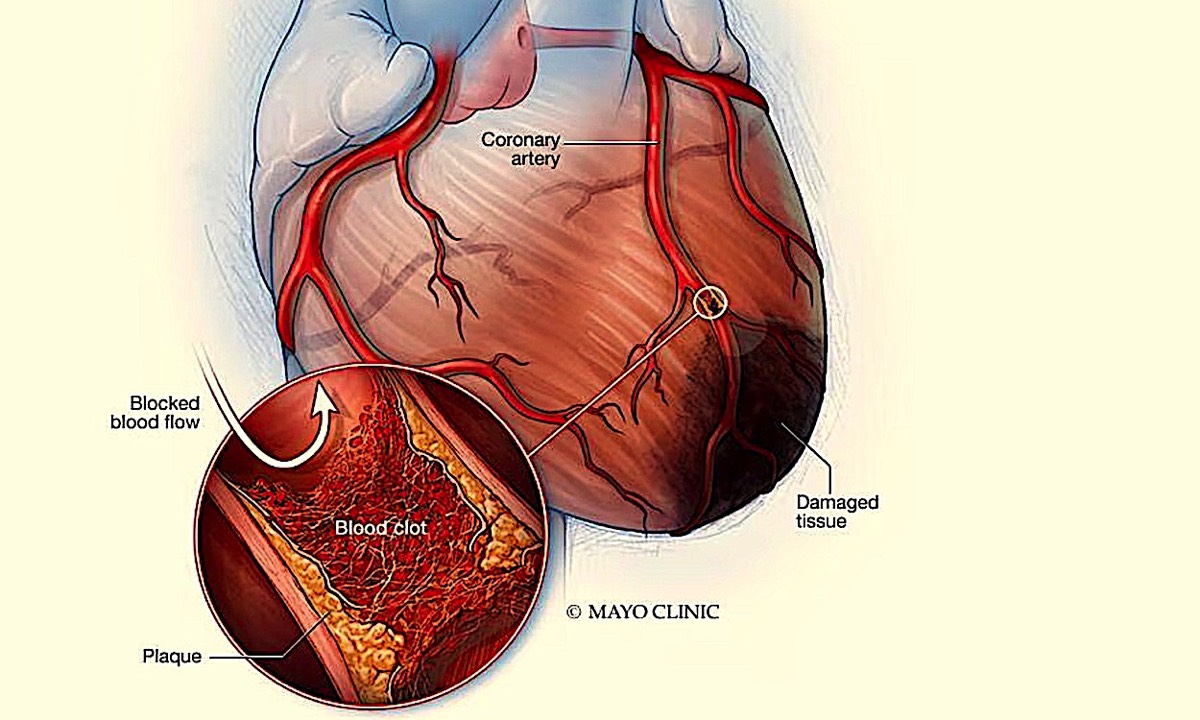

A Heart Attack, also known as myocardial infarction, occurs when blood flow to the heart is suddenly blocked, usually by a blood clot, causing damage to the heart muscle.

A heart attack occurs when the flow of blood to the heart is severely reduced or blocked. The blockage is usually due to a buildup of fat, cholesterol and other substances in the heart (coronary) arteries. The fatty, cholesterol-containing deposits are called plaques. The process of plaque buildup is called atherosclerosis.

mayoclinic.org